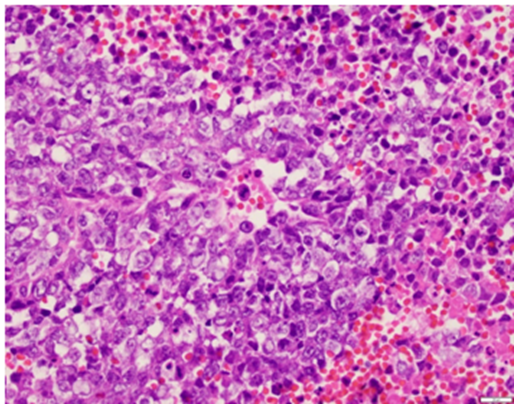

A 52 year old G1P1001 female with a history of hypertension, hyperlipidema, depression, and schizoaffective disorder presented with the primary complaint of a painful left sided vaginal mass. She also complained of irregular heavy menses for the past three months. On pelvic exam, the vaginal mass was diagnosed as a left Bartholin gland abscess that measured 2x3cm and was noted to be indurated. The remainder of the pelvic exam was unremarkable. The patient was offered incision and drainage for which she declined. She was started on Augmentin. Perimenopause was thought to be a contributing factor of the patient’s irregular menstrual pattern. As part of screening guidelines, Papanicolaou smear was performed and was found to be remarkable for atypical glandular cells of undetermined significance. Endometrial biopsy (EMB) was recommended. The patient was lost to follow up for two months. She eventually returned to clinic and reported improvement in the abscess after antibiotics, but recurrence after discontinuation. During her follow up visit, EMB and incision & drainage of the Bartholin abscess with placement of Word catheter was performed. However, due to the exuberant amount of indurated tissue expressed from the Bartholin abscess, a tissue specimen of the Bartholin abscess were sent to pathology for evaluation. The pathology report returned a poorly differentiated malignant neoplasm favoring carcinoma for the Bartholin gland sample as well as the endometrial biopsy sample. The tumor was described as poorly differentiated and consisting of enlarged nuclei with vesicular chromatin, perinuclear clearing, occasional prominent nucleoli, moderate amounts of amphophilic delicate cytoplasm, and increased mitoses (Figures 1 & 2). There was also extensive tumor necrosis seen in the specimens (Figure 3). The patient underwent CT of her chest, abdomen, and pelvis, as well as a PET CT of the skull to thigh. Her CT revealed a 10.8 cm poorly defined endometrial and myometrial neoplasm, with metastatic disease to the right iliac node, right parametrial nodes, periaortic lymph nodes, and bilateral adrenal glands. There were no other significant findings on CT. Her PET scan showed prominent Fluorodeoxyglucose (FDG) activity in the uterine mass and left adrenal mass, with a smaller amount of FDG activity in a large right pelvic lymph node adjacent to the uterine mass, with no other contributory findings (Figure 4). She was referred to the care of medical oncology, and during the patient’s Gynecology Tumor Board case presentation the pathologists concluded that her poorly differentiated cancer was uterine in origin. Due to the extent of metastatic disease she was recommended medical management. She was started on a Paclitaxel and Carboplatin chemotherapy therapy.

Figure 2 High power view of the poorly differentiated tumor, consisting of enlarged nuclei with vesicular chromatin, peri–nuclear clearing, occasional prominent nucleoli, moderate amounts of amphophilic delicate cytoplasm and increased mitoses (H&E, 40x).